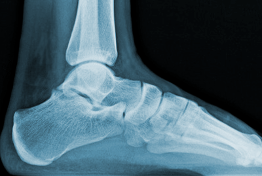

- sa surface articulaire inférieure correspond au "diabolo" (comme au niveau de l'humérus), inversement conformée par rapport à la surface articulaire supérieure du talus, c'est à dire concave d'avant en arrière et convexe transversalement. Sur cette radio de vue latérale, tu vois bien sa concavité vers le bas

5a894281cd6b1_radiochville.png.5946e8dba207ba1441e554848b1e6a32.png